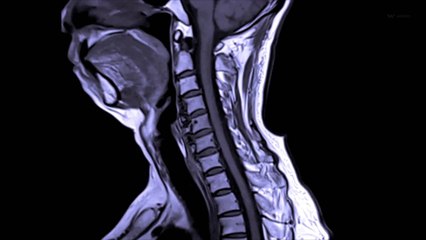

Medical tourism has increased due to spinal cord surgery in India. Injured spinal cord can be cured with the effective spinal cord surgery in India. Experienced spine surgeons provide this surgery at Mumbai, Delhi, Bangalore, and chennai. India has some of the best hospitals and treatment centers in the world with the best facilities. If you want to experience world-class facilities to cure your spinal cord injuries then India would be the best destination to get the treatment done. Spinal cord surgery is medically developed technique for the treatment of injured spinal cord. This surgery alleviates many problems of patient such as relieve pain, restore nerve function, prevent abnormal motion in the spine etc. and ultimately procure a normal life to patient. The surgery of spinal cords is a bit complex process under which surgeon removes the damaged bone and grafts it by either in front of or behind the spine. Nevertheless, sometimes due to considering severity, surgeons use metal plates, screws, or wires in order to stabilize the spine. In India, medical treatment is not only fast but also costs a fraction of what it costs in USA or Europe. Treatment is available in India on very less price comparatively to United States and Europe.Indian hospitals provide utmost good and compassionate care to the international patients for less price spinal cord surgery in India. For positive results get your medical treatment done from the experienced spine surgeons of India. br The well-trained surgeons at hospitals are always there to provide support and care for the patients. To know about cost effective spinal cord surgery in India visit www.dheerajbhojwani.com or mail your queries at contact@dheerajbojwani.